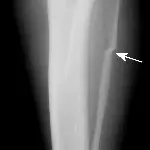

Figure 3A. This series represents an example of a probable fracture that cannot be seen on routine radiographs but that produces secondary signs that can be seen. Slight thickening of the caudal cortex of the tibia (arrow) is present in a dog with left hind limb lameness. The dog is an active, 3-yearold, castrated male black Labrador retriever having lameness for several months but with no prior history of lameness.

Figure 3B. Lameness was persistent, and cortical thickness progressed (arrow) over a 4-month period. Panosteitis might be considered in the differential diagnosis because of the several areas of uptake, although panosteitis does not typically start as a focal unicortical thickening of the bone in a 3-year-old dog.